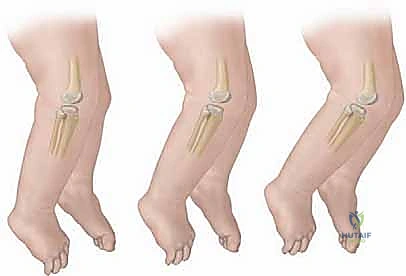

- فرط بسط الركبة (Genu Recurvatum): انحناء الساق إلى الأمام بزاوية غير طبيعية.

- التجبير المتسلسل (Serial Casting): يعتبر العلاج الأساسي. يقوم الدكتور هطيف بإجراء شد لطيف وتدريجي جداً للركبة لثنيها، ثم يضع جبيرة من الجبس أو الفايبر جلاس لتثبيت الركبة في الوضعية الجديدة. يتم تغيير الجبيرة أسبوعياً، وفي كل مرة يتم زيادة زاوية الانثناء (Flexion) تدريجياً حتى تصل الركبة إلى زاوية 90 درجة أو أكثر.

| التوقيت الأمثل | من الولادة وحتى عمر 3 أشهر | بعد عمر 3-6 أشهر (أو فشل العلاج التحفظي) |

| دواعي الاستخدام | الحالات الخفيفة والمتوسطة، غياب المتلازمات | الحالات الشديدة، التيبس المفصلي، متلازمة لارسن |